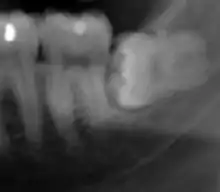

Human jaws and teeth have been shrinking in proportion with the decrease in body size in the last 30,000 years as a result of new diets and technology. There are many individuals today who do not have enough space in their mouths for their third molars (or wisdom teeth) due to reduced jaw sizes. In the twentieth century, the trend toward smaller teeth appeared to have been slightly reversed due to the introduction of fluoride, which thickens dental enamel, thereby enlarging the teeth.[67]